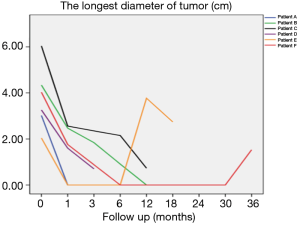

Using the longest diameter of tumor as a longitudinal coordinate (cm), and follow-up time as a horizontal coordinate, change of tumor size is displayed in Figure 6.

Figure 6 also shows that the tumors significantly decreased in all 6 patients after implantation of radioactive particle, which is consistent with the findings in Table 3. The most obvious decrease can be seen in the 6th month after procedure.

Other relevant studies have shown a unique advantage of implantation of radioactive particles in the treatment of lung cancer. In a study by Lu et al. (10), 15 patients with obstructive pneumonia caused by central type lung cancer were given a bronchoscopic implantation of 125I radioactive particles, and followed up in months 2, 6, 12, 18 and 24 after implantation. The median survival was 15.6 months, and the one-year lung recruitment rate was 80.0%, which significantly improved the quality of life. To compare, in our study’s response evaluation from regular follow-up of patients who received the CT-guided implantation of radioactive 125I, it was found that the tumors had significantly shrunk in all 6 patients. Typical cases are illustrated in Figures 4 and 5, and as can be seen in Figure 6, the most obvious reduction of tumor was seen in the 6th month of follow-up. In the 5 patients who were followed up, there were 3 CRs, indicating an RR of 5/5 (100%) and a DCR of 5/5 (100%). This shows that the implantation of radioactive particle achieved the best response within 6 months in the treatment of early lung cancer. In addition, as Figure 3 shows, 5 patients were followed up 1 year after implantation and had a survival rate of 5/5 (100%), 4 patients were followed up 2 years after implantation and had a survival rate of 4/4 (100%), and the longest time after enrollment was up to 3 years and 5 months; at the time of writing, this patient is still alive. The observations above demonstrate the significant efficacy of the implantation of 125I radioactive particles in treatment of early lung cancer.